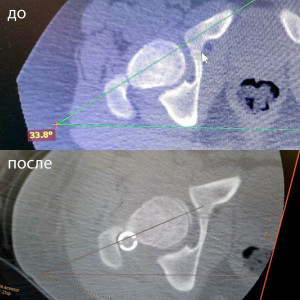

Для коррекции деформации врачи-травматологи-ортопеды впервые в регионе применили блокируемый остеосинтез специальным интрамедуллярным стержнем, который проходит внутри костномозгового канала. Он используется при корригирующей деторсионной остеотомии бедренной кости, направленной на исправление деформации кости. До операции угол деформации составлял 34 градуса, после - 19 градусов.